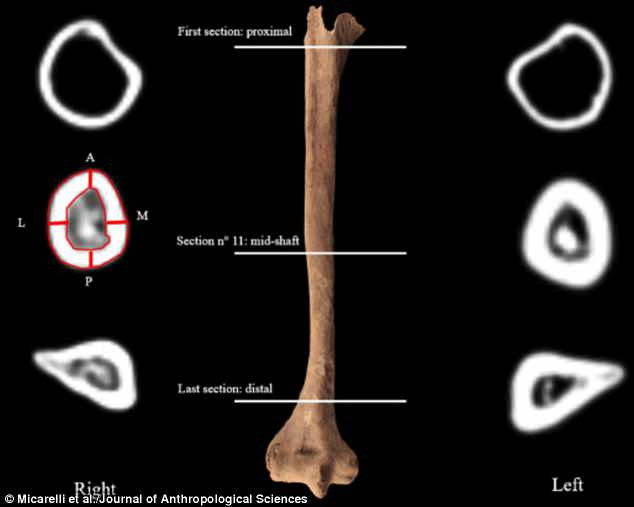

Nhóm nghiên cứu dẫn đầu bởi nhà khảo cổ Ileana Micarelli tại Đại học Sapienza ở Rome cho hay vết thương của người chiến binh thời Trung cổ trên hình thành do tác động vật lý. Tuy nhiên, nguyên nhân hay cách thức người này bị thương vẫn là bí ẩn.

Thêm nữa, chuyên gia còn phát hiện phần cuối hai xương cẳng tay của người đàn ông trên hình thành sẹo và gai xương ở xương trụ. Điều này phù hợp với ảnh hưởng tới cơ thể khi lắp bộ phận giả tạo ra.